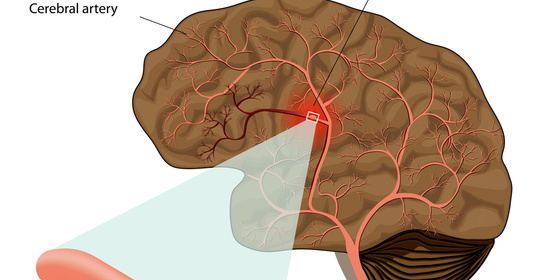

腦血管破裂後遺症的症狀、前兆、治療和預防

腦血管瘤手術後遺症的治療與預防:症狀、前兆與措施

腦動脈瘤破裂後遺症的防治與管理:症狀、前兆、治療與預防